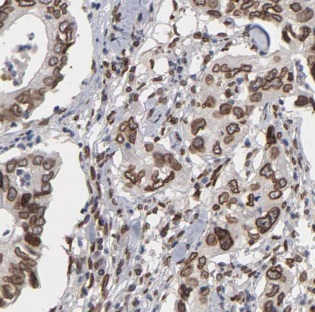

| 验证图片 | Immunohistochemistry of paraffin-embedded human lung cancer using FNab00312(ALKBH3 antibody) at dilution of 1:50 mouse heart tissue were subjected to SDS PAGE followed by western blot with FNab00312(ALKBH3 antibody) at dilution of 1:1000 |